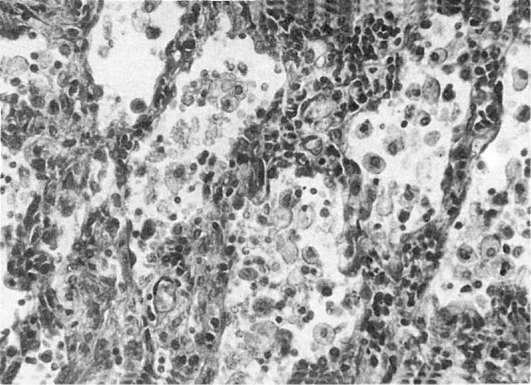

Рис. 189. Хроническая

Этиология. Причина возникновения идиопатического фиброзирующего альвеолита не установлена, предполагается вирусная его природа. Среди этиологических факторов экзогенного аллергического альвеолита велико значение ряда бактерий и грибов, пыли, содержащей антигены животного и растительного происхождения, медикаментозных препаратов. Развитие токсического фиброзирующего альвеолита связано главным образом с воздействием лекарственных средств, обладающих токсическим пневмотропным действием

Патологическая анатомия. На основании изучения биоптатов легких установлены три стадии морфологических изменений легких при фиброзирующем альвеолите (пневмоните): 1) альвеолит (диффузный, или гранулематозный); 2) дезорганизация альвеолярных структур и пневмофиброз; 3) формирование сотового легкого.

В стадию альвеолита, которая может существовать длительное время, происходит нарастающая диффузная инфильтрация интерстиция альвеол, альвеолярных ходов, стенок респираторных и терминальных бронхиол нейтрофилами, лимфоцитами, макрофагами, плазматическими клетками. В таких случаях говорят о диффузном альвеолите (рис. 190). Нередко процесс принимает не диффузный, а очаговый гранулематозный характер. Образуются макрофагальные гранулемы как в интерстиции, как и в стенке сосудов. Тогда говорят огранулематозном альвеолите. Клеточная инфильтрация ведет к утолщению альвеолярного интерстиция, сдавлению капилляров, гипоксии.

190. Фиброзирующий альвеолит

сте альвеол появляются кисты с фиброзно-измененными стенками. Как правило, развивается гипертензия в малом круге кровообращения. Гипертрофия правого сердца, которая появляется еще во второй стадии, усиливается, в финале развивается сердечно-легочная недостаточность.